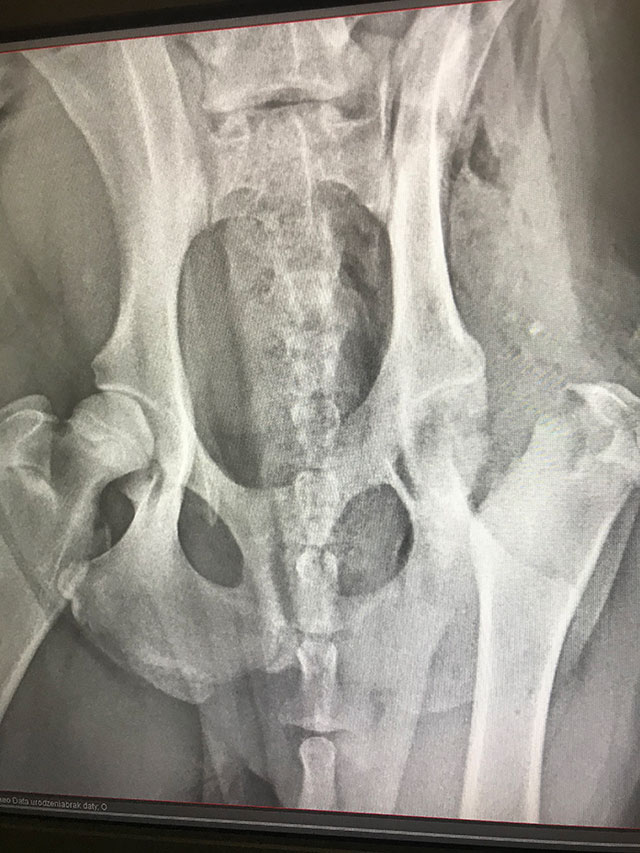

FHO

• FHO

(Femoral Head Osteotomy)

Zabieg polegającym na resekcji główki kości udowej.